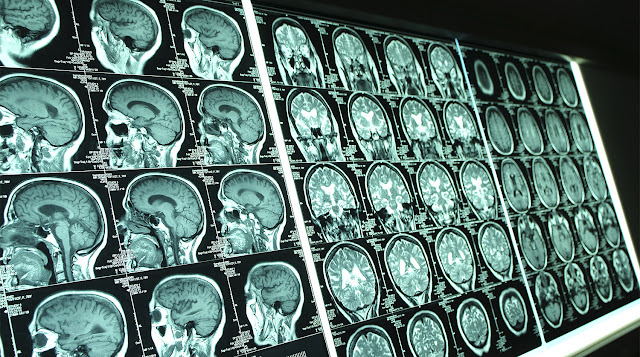

В рамках оценки психического состояния пациентки врачи также провели МРТ. Оно и выявило настоящую причину появления голосов свыше – опухоль головного мозга, злокачественную глиому.

Опухоль затронула участки мозга, участвующие в обработке звука и области, влияющие на эмоции. Все это в совокупности и привело к слуховым галлюцинациям и ощущению «благословенности», считают врачи.

Ранее не отличавшаяся особой религиозностью женщина часами штудировала Библию и другие священные книги. Близкие друзья и родственники предположили, что у женщины так могла проявляться депрессия — в тот период она заботилась о страдавшем от рака родственнике. Однако результаты МРТ выявили несколько пораженных участков в мозге. Биопсия показала, что у пациентки глиобластома.